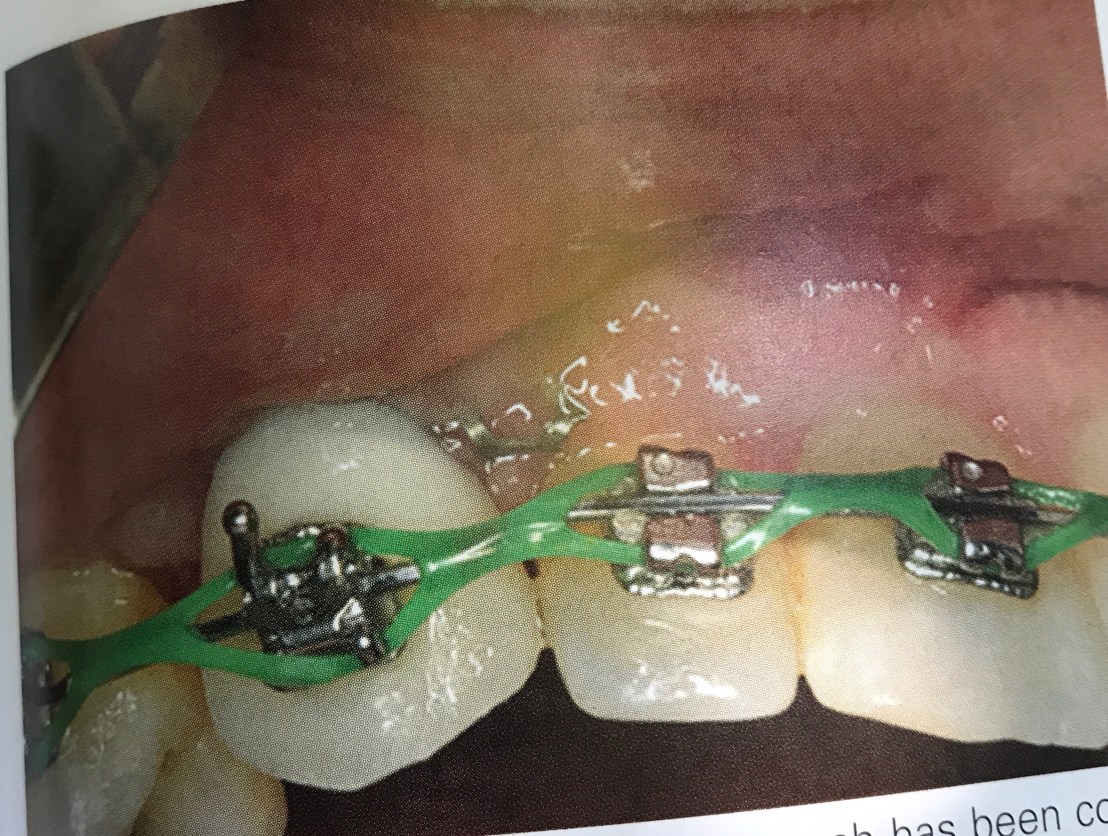

รูปแสดงการ Splint Implant กับฟันธรรมชาติ ที่เกิด failure จากความไม่ไปด้วยกันของการ movement ที่ต่างกัน คือ ฟันธรรมชาติมีแนวโน้มจะ ขยับ มากกว่า และยิ่งถ้าเกิด lateral movement ก็ยิ่งเคลื่อนได้มากจน Cement และ abutment loose